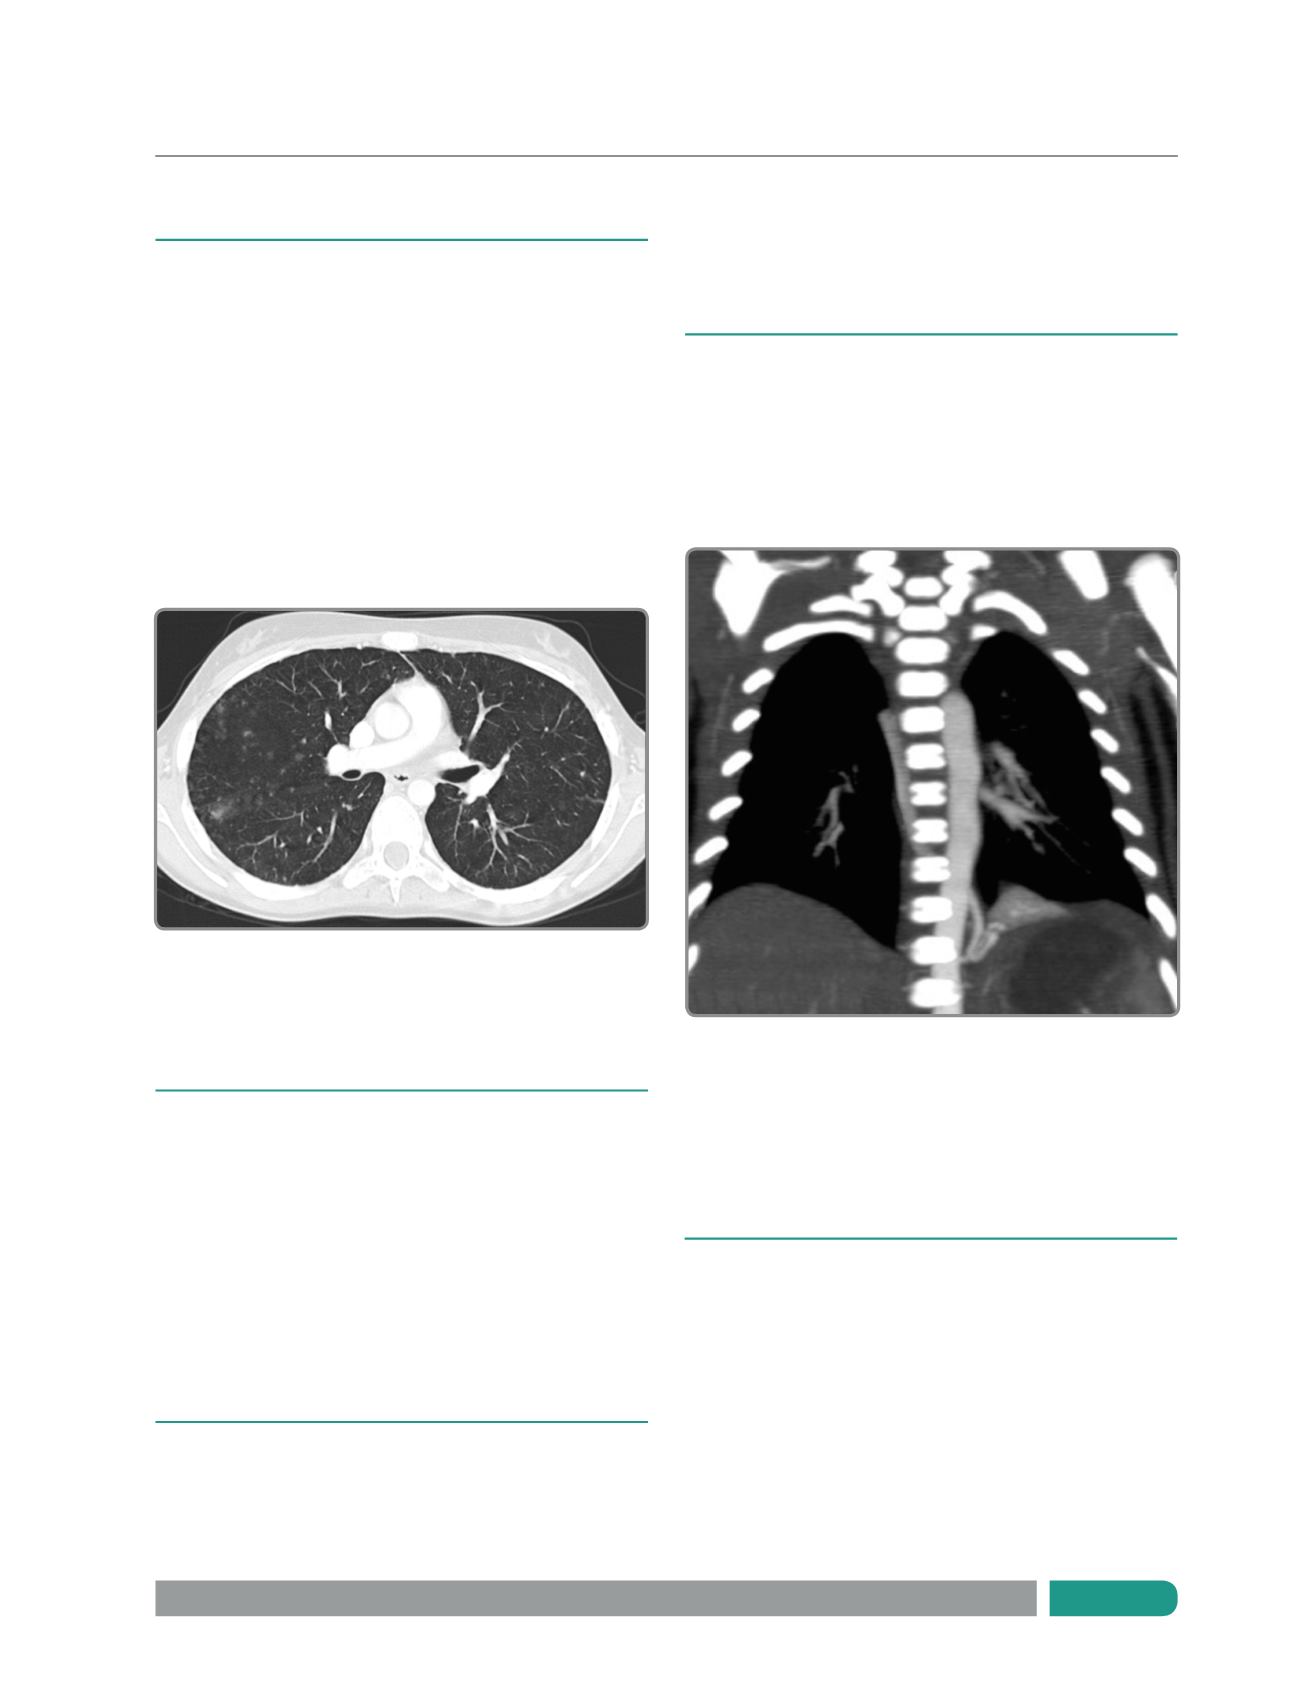

NÓDULOS PULMONARES

La TCMC ha mejorado en más de un 10% la

detección de nódulos pulmonares con respecto a la tomografía

convencional. En general, el estudio se realiza en pacientes

en apnea en los que se hacen cortes secuenciales, sin uso de

contraste (Figura 2). En niños que no pueden realizar apnea se

obtiene con respiración tranquila, lo que no produce una pérdida

significativa de información en la detección de metástasis

pulmonares.

En general, se usa reconstrucciones con solapamiento

de las imágenes de un 50% lo que mejora la pesquisa de nódulos

y disminuye posibles artefactos.

Las reconstrucciones en los distintos planos del espacio

permiten valorar la relación que tienen los nódulos con las

distintas estructuras anatómicas y vasculares (7).

Figura 3.

Reconstrucción coronal que muestra el vaso nutricio que emerge

de la aorta torácica hacia el secuestro pulmonar basal izquierdo.

Figura 2.

La imagen muestra múltiples metástasis pulmonares de pequeño

tamaño diseminadas en ambos campos pulmonares.